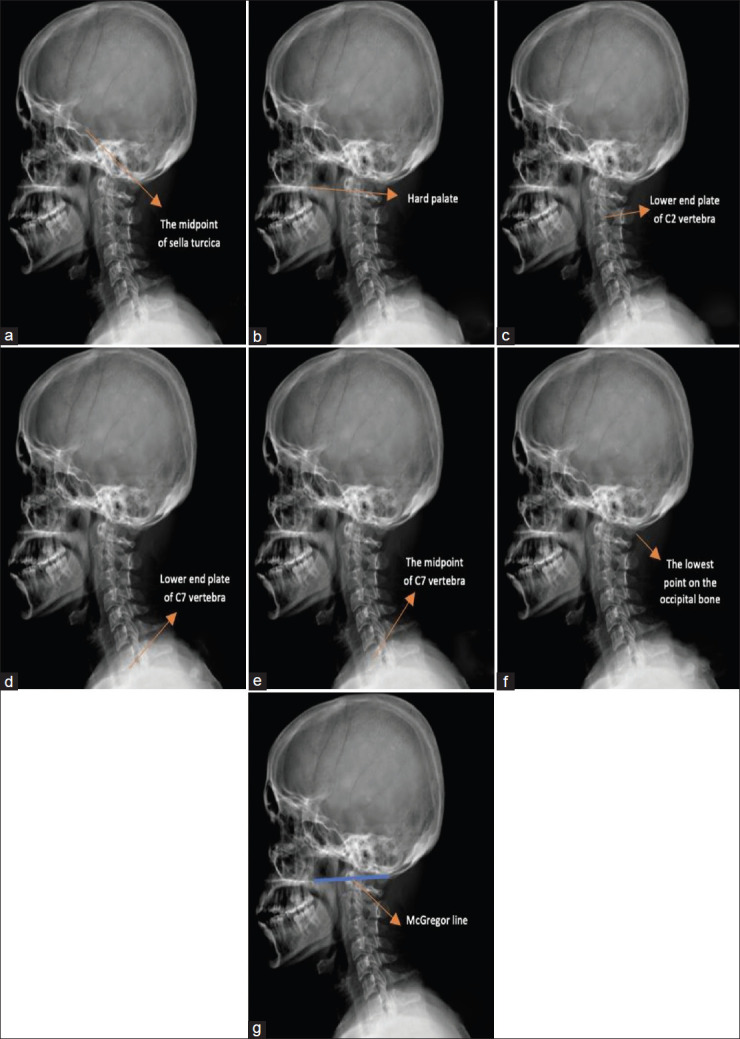

Materials and methods: This retrospective study included 102 CM patients and 71 healthy controls. Radiological measurements were obtained from cervical X-rays, with seven reference points used to calculate angles related to head positioning and cervical curvature. Angular parameters, including cranial incidence (CI), cranial slope (CS), cranial tilt (CT), C7 slope (C7S), and spinocranial angle (SCA), were analyzed to determine correlations with the COG of the head. Statistical analyses were performed using t-tests, ROC analysis, and Pearson/Spearman correlation tests.